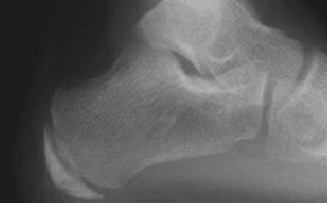

| What disease is this? | Sever's disease |